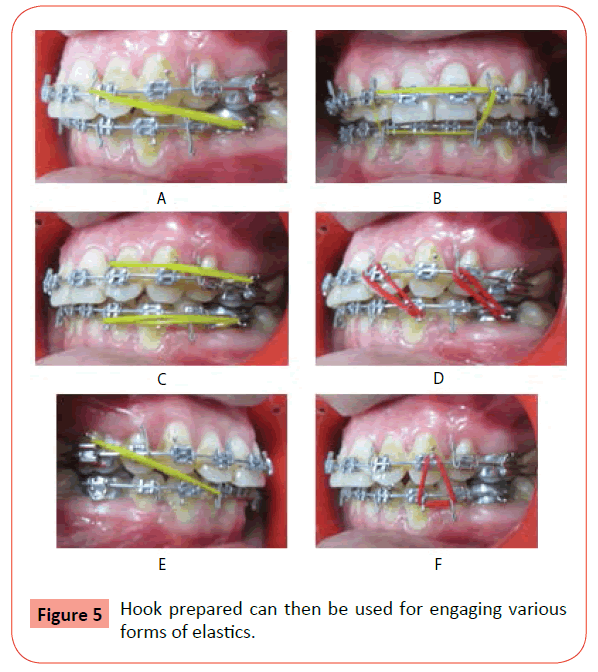

finishing and detailing in orthodontics PPT cheap, Orthodontic finishing Settling elastics Rubber Bands cheap, Orthodontic Update Use of Elastics in Orthodontics cheap, Occlusal settling phase. 5 16 cheap, Elastics in Orthodontics part I PPT cheap, Orthodontic Update Use of Elastics in Orthodontics cheap, Braces finishing Class 3 settling Elastics cheap, Orthodontic Elastics Saudi Orthodontics Club cheap, The third stage of comprehensive treatment PPT cheap, Dental Update Wearing elastics in the 21st century cheap, Elastics and Elastomeric in Orthodontics Practice cheap, Elastic Wear PORTAL MyHEALTH cheap, Dr. Mirna Nguyen last step towards that cheap, Elastics in Orthodontics part I PPT cheap, Customized Ligature Hook A Noble Approach for Engaging Elastic in cheap, Correction of a Full Cusp Class II Malocclusion and Palatal cheap, Camoufl age of Class II Division I malocclusion with retrusion cheap, Optimization of Orthodontic Elastics Langlade PDF Dentistry cheap, Orthodontic Update Use of Elastics in Orthodontics cheap, Class 2 elastics with molar stops. Download Scientific Diagram cheap, Intermaxillary Elastics with Clear Aligners Types Use cheap, Three Reasons I Use Aligner Auxiliaries Dr Aisling Byrne s cheap, Elastics in Orthodontics part I PPT cheap, Delta Triangle Vertical Settling Elastics Orthodontics cheap, DT News International All buttoned up Styling your plastic cheap, Retention Looking back over a 50 year practice career ScienceDirect cheap, Box elastics with class III vector on the right side and class II cheap, Settling Elastics In Orthodontics Buy Now Deals 55 OFF www cheap, Orthodontic Update Use of Elastics in Orthodontics cheap, Ligation ties in orthodontics cheap, Before and Afters Specialist Orthodontist in London Origin cheap, Orthodontic Elastic Wear Fact Sheet cheap, Mini implant supported Molar Distalization Semantic Scholar cheap, Understanding the Uses and Importance of Orthodontic Elastics cheap, Elastics in Orthodontics part I PPT cheap.

finishing and detailing in orthodontics PPT cheap, Orthodontic finishing Settling elastics Rubber Bands cheap, Orthodontic Update Use of Elastics in Orthodontics cheap, Occlusal settling phase. 5 16 cheap, Elastics in Orthodontics part I PPT cheap, Orthodontic Update Use of Elastics in Orthodontics cheap, Braces finishing Class 3 settling Elastics cheap, Orthodontic Elastics Saudi Orthodontics Club cheap, The third stage of comprehensive treatment PPT cheap, Dental Update Wearing elastics in the 21st century cheap, Elastics and Elastomeric in Orthodontics Practice cheap, Elastic Wear PORTAL MyHEALTH cheap, Dr. Mirna Nguyen last step towards that cheap, Elastics in Orthodontics part I PPT cheap, Customized Ligature Hook A Noble Approach for Engaging Elastic in cheap, Correction of a Full Cusp Class II Malocclusion and Palatal cheap, Camoufl age of Class II Division I malocclusion with retrusion cheap, Optimization of Orthodontic Elastics Langlade PDF Dentistry cheap, Orthodontic Update Use of Elastics in Orthodontics cheap, Class 2 elastics with molar stops. Download Scientific Diagram cheap, Intermaxillary Elastics with Clear Aligners Types Use cheap, Three Reasons I Use Aligner Auxiliaries Dr Aisling Byrne s cheap, Elastics in Orthodontics part I PPT cheap, Delta Triangle Vertical Settling Elastics Orthodontics cheap, DT News International All buttoned up Styling your plastic cheap, Retention Looking back over a 50 year practice career ScienceDirect cheap, Box elastics with class III vector on the right side and class II cheap, Settling Elastics In Orthodontics Buy Now Deals 55 OFF www cheap, Orthodontic Update Use of Elastics in Orthodontics cheap, Ligation ties in orthodontics cheap, Before and Afters Specialist Orthodontist in London Origin cheap, Orthodontic Elastic Wear Fact Sheet cheap, Mini implant supported Molar Distalization Semantic Scholar cheap, Understanding the Uses and Importance of Orthodontic Elastics cheap, Elastics in Orthodontics part I PPT cheap.